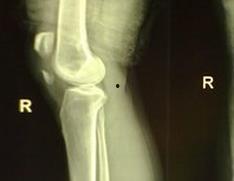

首先,咱们得弄清楚什么是髌骨骨折。髌骨,也就是我们常说的膝盖骨,它是人体最大的籽骨,位于膝盖前方。髌骨骨折,顾名思义,就是膝盖骨发生了断裂。这种情况可能是因为跌倒、撞击或者剧烈运动造成的。